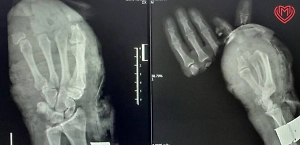

«Предварительно установлено, что при спуске с горки мизинец правой руки ребёнка попал в щель, в результате чего произошла травматическая ампутация пальца, после чего малолетняя была госпитализирована в медицинское учреждение», — говорится в сообщении.

Ранее Life.ru писал, как в Детском центре Рошаля медики спасли изувеченный палец девочки, который чуть не оторвало эскалатором. Ребёнок засунул руку в движущуюся ленту и повредил указательный палец на левой руке. Конечность собирали по осколкам.